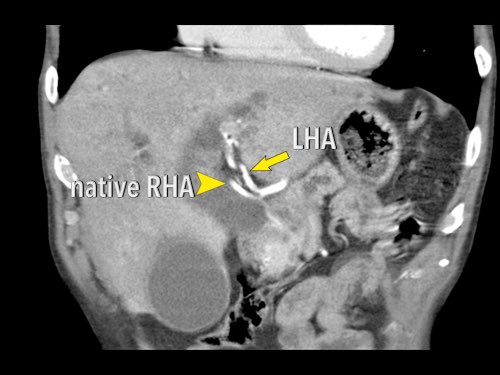

Ở những bệnh nhân dự kiến phẫu thuật tụy, điều quan trọng là cần đặc biệt chú ý tìm kiếm nguyên ủy bất thường của động mạch gan phải hoặc động mạch gan chung.

Các động mạch này xuất phát từ phía phải của động mạch mạc treo tràng trên (SMA) và đi qua vùng lân cận đầu tụy, làm tăng nguy cơ xâm lấn của khối u hoặc tổn thương do phẫu thuật.

Tần suất được ghi nhận của các bất thường đặc hiệu này lần lượt là 11-21% và 0,5-5%.

Hình CT axial cho thấy một động mạch gan phải phụ thêm (mũi tên vàng) đi qua vùng lân cận một khối giảm tỷ trọng ở đầu tụy (đầu mũi tên).

Sự liên quan mạch máu được đánh giá rõ hơn trên ảnh tái tạo mặt phẳng đứng dọc. Có sự áp sát 90 – 180° của động mạch gan phải thay thế (mũi tên trắng) bởi ung thư biểu mô tuyến đầu tụy (đầu mũi tên trắng).

Động mạch gan trái nguyên bản đi theo hướng ra trước hơn, tĩnh mạch cửa nằm ở giữa.

Cuộc phẫu thuật là cắt bỏ diện R1.

Các hình ảnh axial của cùng bệnh nhân có chú thích.